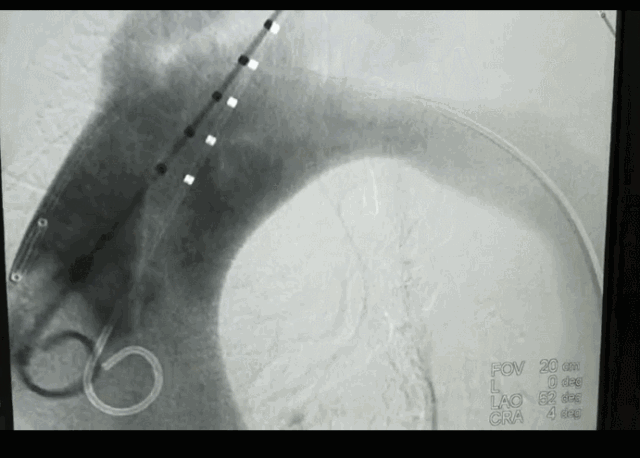

由于患者主动脉弓支架锚定区直径近36mm,需要大型号的支架,整个南阳市内没有,经联系只有郑州有,大雪封路,没有班车及快递,马上启动应急预案,连夜从郑州坐火车把支架运回,在住院第二天上午急诊手术,行腋腋动脉转流+主动脉覆膜支架植入+左锁骨下动脉弹簧圈封堵术,术后患者恢复顺利。